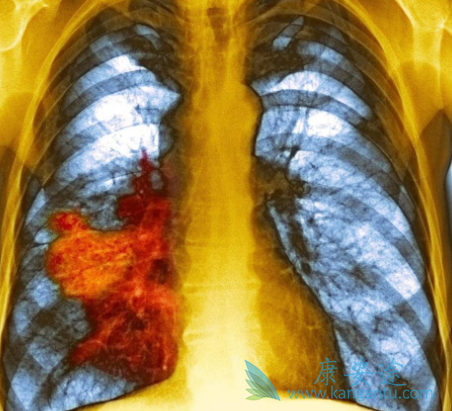

来自于国外的晚期肺癌治疗研究,多与放疗联合结果报告,患者耐受性良好且有一定的放疗増敏作用,几乎未见皮疹的发生。本例患者发病时即为晚期,转移广泛,特别是多发脑转移,失去手术机会采用尼妥珠单抗联合GP方案化疗,2个周期化疗后疗效评价PR,肿瘤明显缩小。

4个周期化疗后肿瘤进一步缩小,6个周期化疗后脑部病灶进一步缩小,其他病灶全部消失。治疗8个周期后,除脑部残存病灶也完全消失。治疗期间患者耐受性良好,未出现痤疮样皮疹及其他严重不良反应。提示尼妥珠单抗联合本方案化疗安全、低毒。尼妥珠单抗在我国获批适应症是鼻咽癌,商品名为泰欣生。